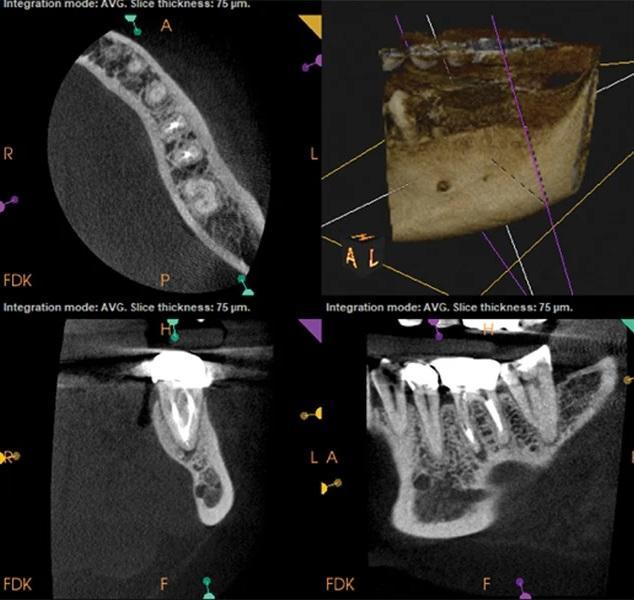

Наличие четко определяемых проблем или технических ошибок при первичном эндодонтическом лечении также играет важную роль в прогнозировании исходов повторного лечения. Исследования показывают, что результаты повторного лечения часто обратно пропорциональны качеству первичного лечения. Когда причины неудачи первичного лечения очевидны и поддаются коррекции (например, пропущенный канал или неполная обтурация), прогноз повторного лечения, как правило, более предсказуем, поскольку возможна целенаправленная коррекция выявленных дефектов (фото 2–5).

Фото 2–5. Клинический случай 2. Выявляемые причины неудачи первичного эндодонтического лечения, как правило, ассоциированы с более предсказуемым исходом повторного лечения.

Фото 3: Предоперационная КЛКТ. Отмечаются неполное пломбирование и периапикальная радиолюцентность, связанные с медиальным каналом.

Фото 5: КЛКТ через 3 месяца после лечения. Отмечается регресс периапикальной патологии в области медиального канала.